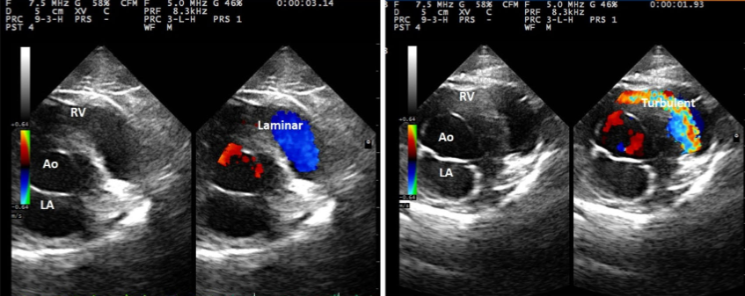

간혹 방사선 검사나 임상증상, 심지어 심장 초음파 검사에서도 정상인데 심잡음이 들리거나

청진상에서는 정상이었는데 심장 초음파 검사상 TR flow가 관찰되는 환자의 경우 혹시 compression에 의해 발생한 의인성 거짓 심잡음은 아닌지 생각해 보라는 논문

환자가 검사에 호응하지 않는경우 검사자의 긴장도에 따라 그럴 수도 있다.